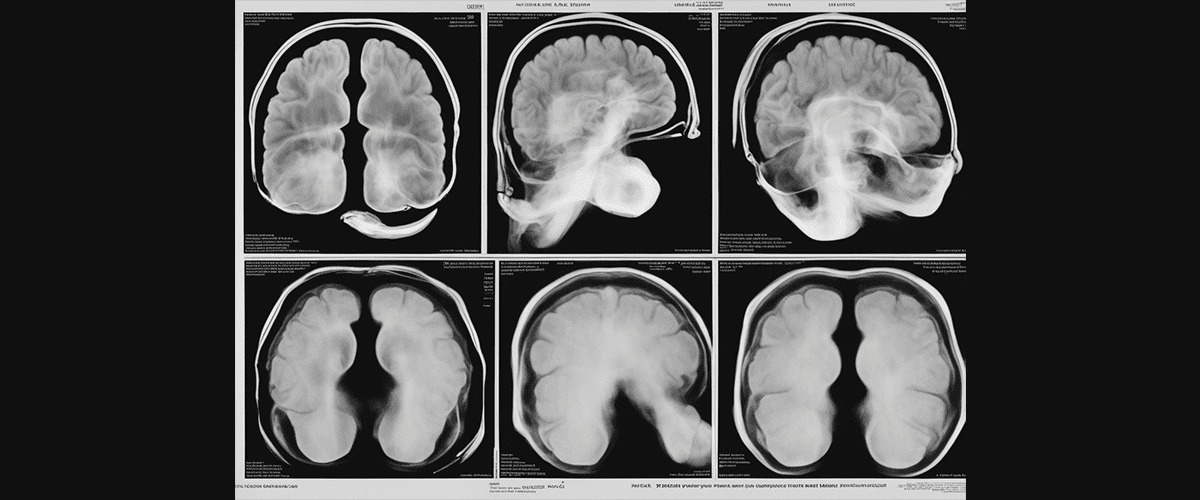

Parkinson disease – A neurodegenerative movement disorder

Parkinson disease is a slowly progressive neurodegenerative disorder diagnosed in roughly 90,000 people a year in the United States and is characterized by:

The pathophysiology is characterized by neuronal cell death in the brain areas of the locus coeruleus and substantia nigra where the neurotransmitter Dopamine is produced for use by the basal ganglia which generally governs voluntary motor control.  Lewy bodies contain alpha synuclein form within neurons and accumulate causing dysfunction.  Alpha synuclein is an antimicrobial peptide similar to beta amyloid, that collects in the brain.  The disease also depletes dopamine from the dopaminergic system which ultimately causes the movement disorder.